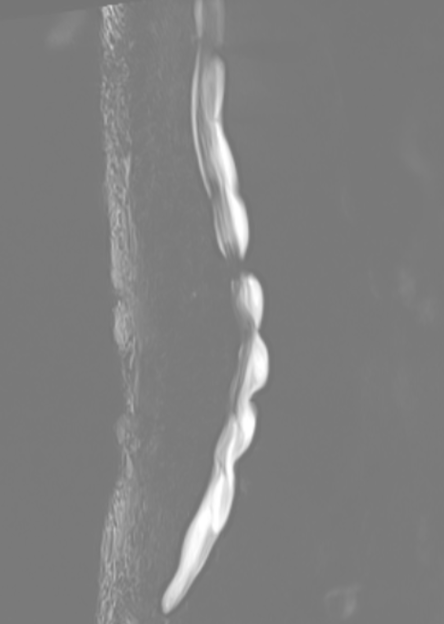

第1腰椎陳旧性圧迫骨折・腰椎の各椎間板狭小化/椎体変形/骨曲形成/ヘルニア/黄色靭帯肥厚/脊柱管狭窄症・股関節炎